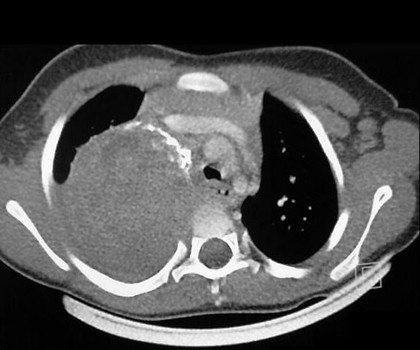

Далее определяют визуально наличие опухоли с помощью рентгенографии, компьютерной томографии, МРТ, ультразвукового исследования.

Диагностика с помощью МРТ дает более точную картину опухоли.

нейробластома на диагностическом снимке

грудной клетки, которая сможет отыскать локализованную там опухоль; - КТ, МРТ

и другие методы.